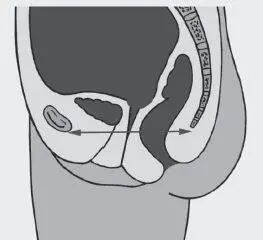

Рис. 1. Нормальное положение таза

Рис. 2. Нормальное положение таза

В норме гравитационная вертикаль проходит через промежность и отверстие большого Родничка (Рис. 2).

Именно такое положение обеспечивает нормальное состояние лобково-копчиковой мышцы, которая простирается от лобковой кости до копчика, поддерживает анус и остальные граничащие с ним внутренние органы, не давая им опуститься. Находится она на расстоянии 2–3 см от кожного покрова. Мышца управляется нервом, который контролирует активность ануса и половых органов, посылая сигналы от них в мозг и передавая их обратно.

Лобково-копчиковая мышца также связана с тазовым внутренним нервом, ответвление которого у женщин соединяет нижнюю часть позвоночника с маткой и мочевым пузырем, ау мужчин – с простатой и мочевым пузырем. Соответственно, правильное положение костей таза гарантирует здоровый физиологический тонус мышцам тазового дна, что обеспечивает здоровье урогенитальной системы человека.

Все отклонения в положении таза: высокое или низкое положение копчика, смещение лобковой кости в результате травм и пр. (Рис. 3–4), перерастягивают мышцы тазового дна, либо, напротив, лишают их опоры, в результате чего они провисают растянутым гамаком. Эти отклонения фасциально передаются по телу, заставляя его искажаться и искать пути компенсации для сохранения вертикального положения.